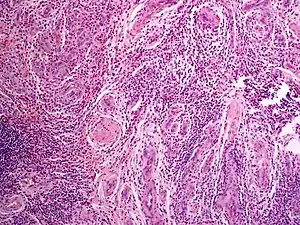

Angiolymphoid hyperplasia with eosinophilia

Angiolymphoid hyperplasia with eosinophilia (also known as:[1] "Epithelioid hemangioma," "Histiocytoid hemangioma," "Inflammatory angiomatous nodule," "Intravenous atypical vascular proliferation," "Papular angioplasia," "Inflammatory arteriovenous hemangioma," and "Pseudopyogenic granuloma") usually presents with pink to red-brown, dome-shaped, dermal papules or nodules of the head or neck, especially about the ears and on the scalp.[2]